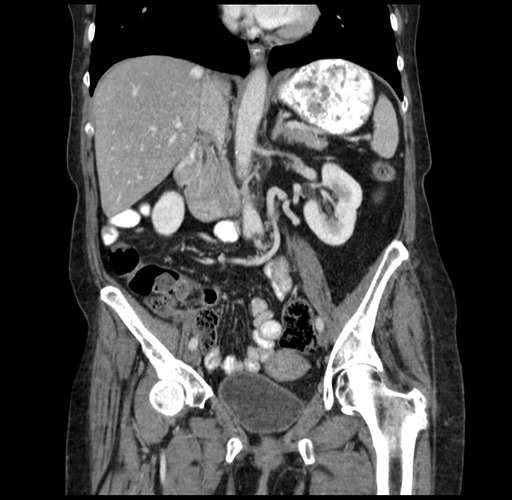

Pre-Chemo: Coronal Venous

Coronal Venous